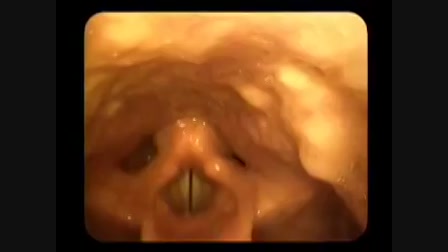

hüvelygomba